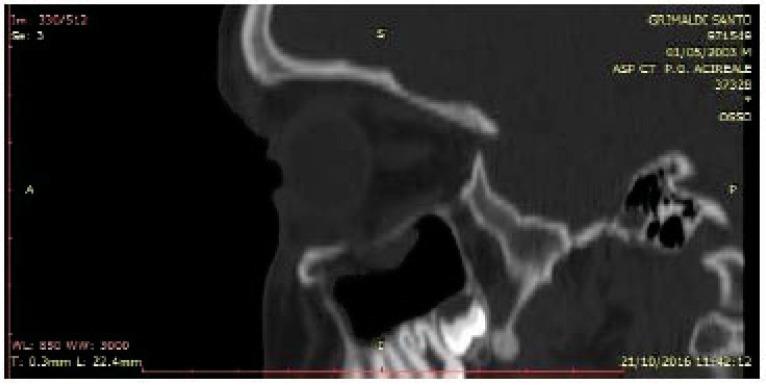

In the years between 2001 and 2016, about 1200 patients with midfacial trauma and about 100 patients involving the orbital floor have been evaluated. All those patients underwent the surgical fracture reduction and a CT scan follow up control at one month, three months, six months and one year.

在2001年至2016年期间,对约1200例面中部创伤患者和约100例涉及眶底的患者进行了评估。所有这些患者均接受了手术骨折复位,并在1个月、3个月、6个月和1年时进行了CT扫描随访控制。